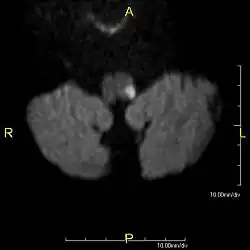

![]() Obraz MRI lewostronnego zawału grzbietowo-bocznej części rdzenia przedłużonego | |

Zespół Wallenberga (zespół boczny opuszki, ang. lateral medullary syndrome, Wallenberg's syndrome, posterior inferior cerebellar artery syndrome) – zespół neurologiczny spowodowany zamknięciem tętnicy móżdżkowej tylnej dolnej (PICA).